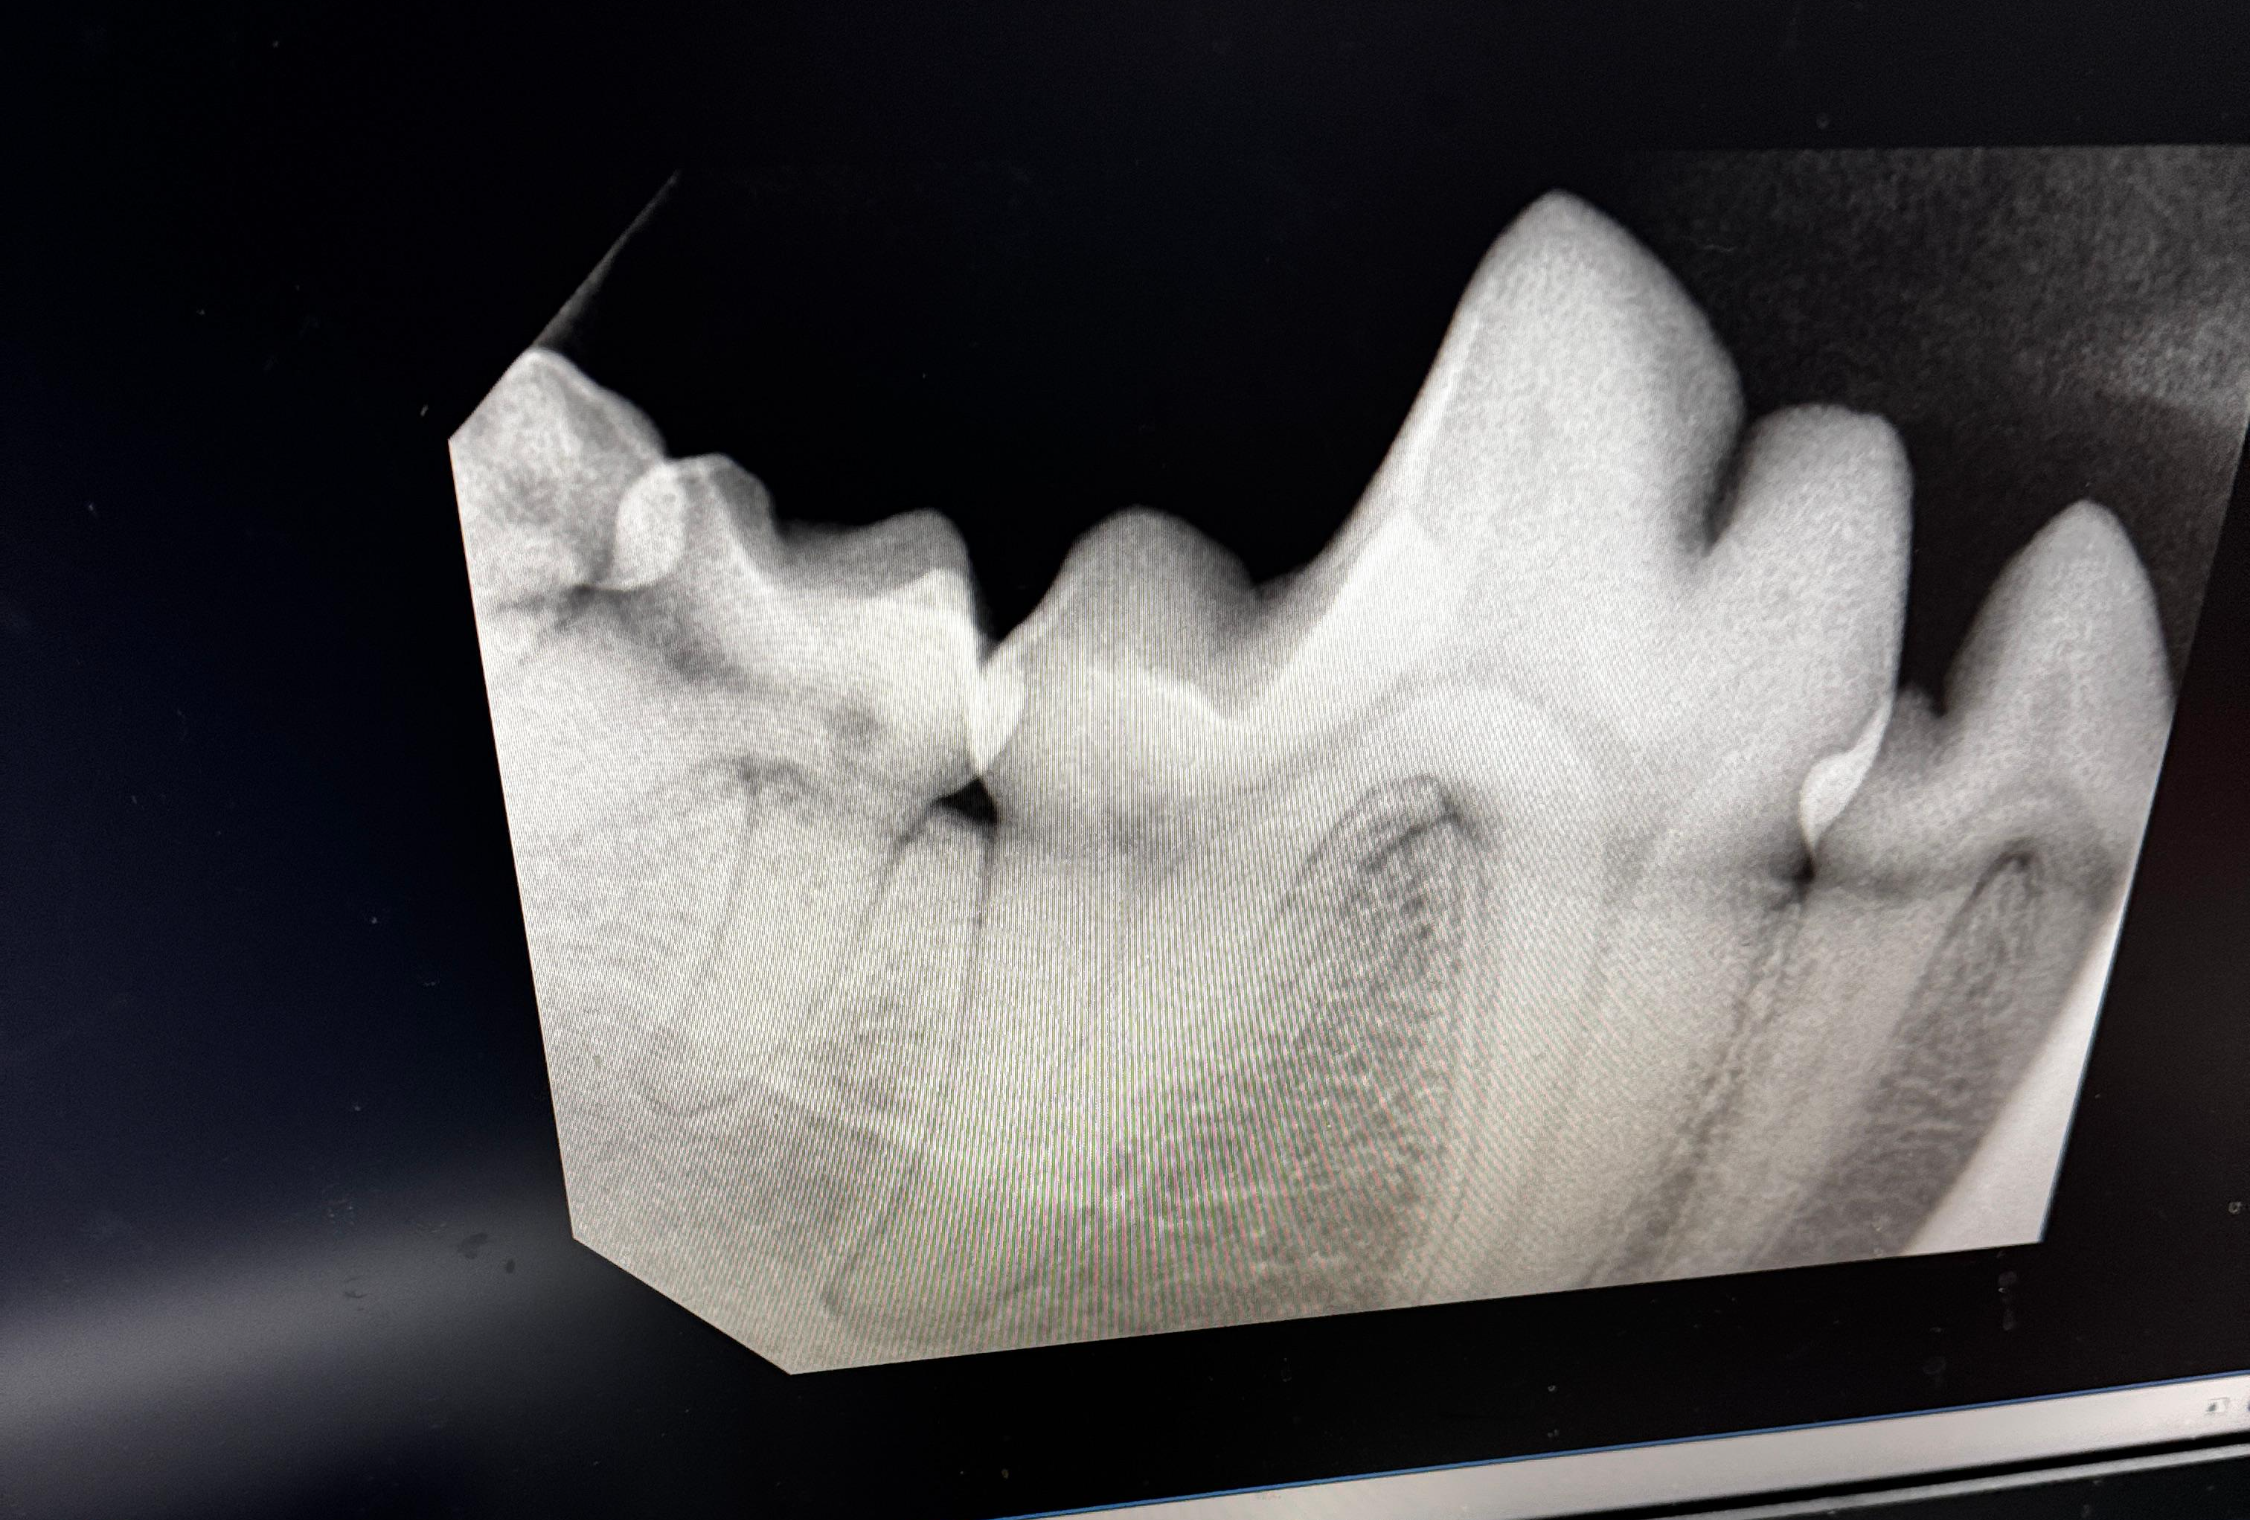

② 구강 엑스레이를 통한 치조골 분석 (가장 중요!)

겉으로 보이는 잇몸은 '살'에 불과합니다. 진짜 중요한 것은 치아를 잡고 있는 '뼈(치조골)'입니다. 정상 범위: 엑스레이상에서 치조골의 높이가 치근(뿌리)의 상당 부분을 감싸고 있다면 보존이 가능합니다. 발치 대상: 치조골이 녹아내려 치아 뿌리가 절반 이상 드러나고 뼈 사이가 비어 있다면, 이는 통증의 원인이 되므로 발치를 권장합니다.